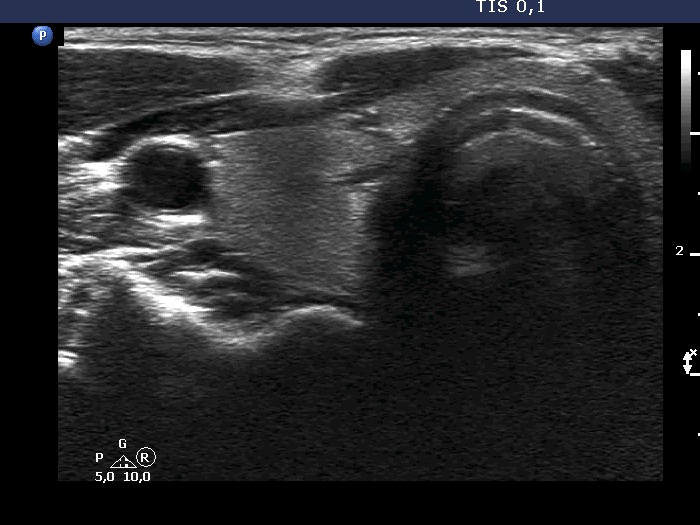

Ultrasonography. The thyroid was echonormal. On transverse scan, a minimally-moderately hypoechoic areas was found in the ventral part of the right lobe. Just ventral to this area, there was a thick connective tissue band within the strap muscle. This area could not be detected on longitudinal scan.

Comment. Anatomical structures ventral to the thyroid influence the penetration of ultrasound wave. The two most common examples are the acoustic shadowing caused by macrocalcifications and the opposite, the acoustic amplification dorsal to cystic fluid. In this case, the thickened connective tissue impaired the penetrance of ultrasound wave and decreased the echogenicity of the thyroid dorsal to this thickening.